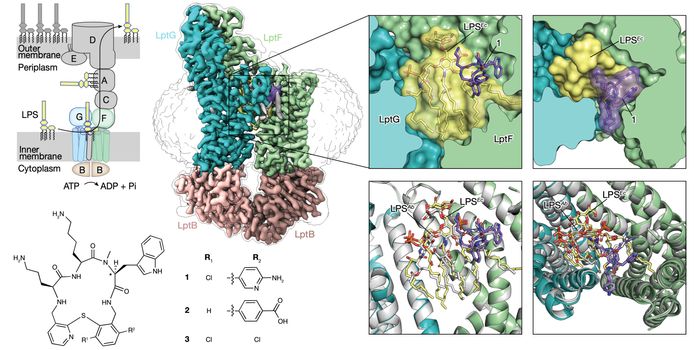

SEP 09, 2024Drug Discovery & DevelopmentThere’s No Turning Back Not long ago, solving the crystal structure of a protein required an entire PhD. Gro ...

AUG 06, 2024Drug Discovery & DevelopmentResearchers have developed a compound that can clear multiple strains of bacteria in mice, including those that lead to ...